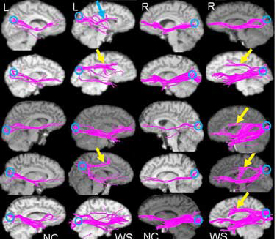

As expected, the researchers found fiber tract abnormalities connected to the regions implicated in the earlier MRI/fMRI studies. These included excess fiber bundles, skewed fiber orientation and direction, and lopsidedness in the balance of white matter between the hemispheres (see graphic below).

Diffusion tensor imaging scans show differences in brain wiring between Williams Syndrome patients (WS) and paired normal controls (NC). Four patients showed aberrant long-distance connections, or fiber tracts, coursing from the back of the brain to an area in the top front of the brain, particularly in the right hemisphere (yellow arrows). One patient had an aberrant tract projecting to a somewhat lower area in the mid front of the brain (blue arrow). Each row shows left and right views of long-distance fiber tracts in a patient and matched control set, as revealed by diffusion tensor MRI.

Source: Karen Berman, M.D., Stefano Marenco, M.D., NIMH Genes Cognition and Psychosis Program